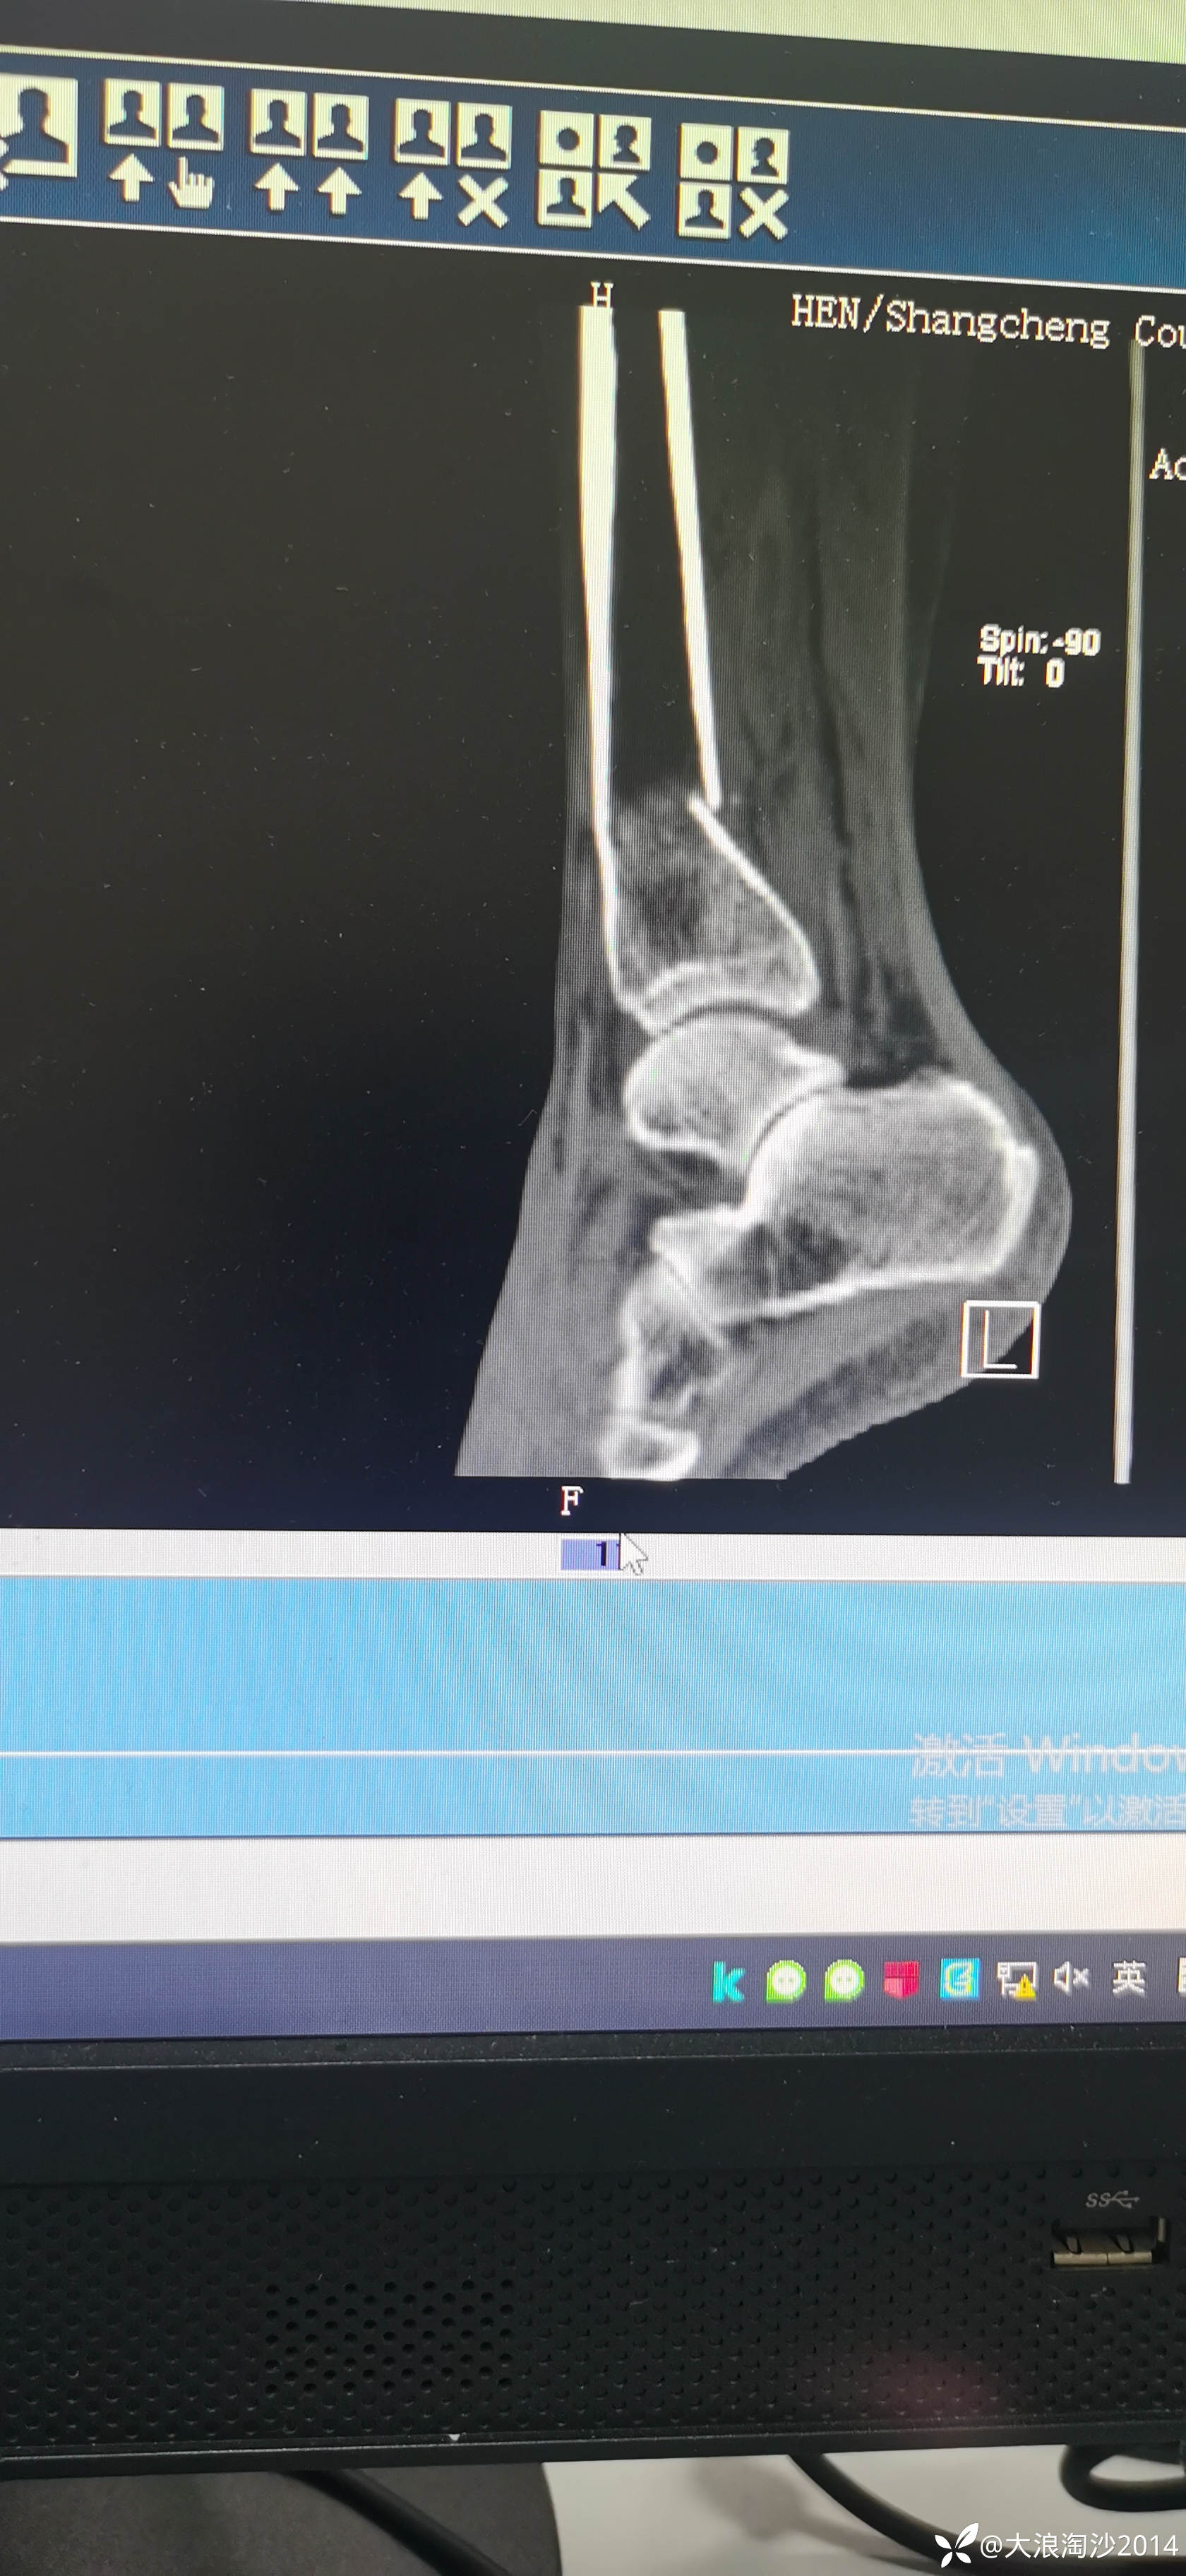

一65岁女性患者,偏瘦,体重75斤,车祸外伤致左胫腓骨远端骨折,入院后消肿后,病人可以用皮包骨头形容,考虑胫骨远折端不适合用内侧插板(mippo技术),病人太瘦,如取两个切口分别处理胫腓骨,切口容易出现问题,因此采用前外侧一个切口处理胫腓骨远端骨折(片子顺序上传有点乱)